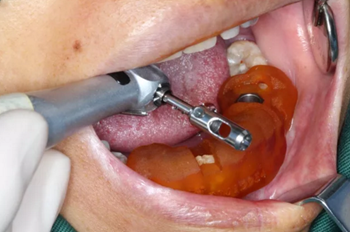

1.碘伏浸泡消毒后的導(dǎo)板在患者口內(nèi)試戴,就位準(zhǔn)確、十分穩(wěn)固。

2.使用牙齦環(huán)切刀施行不翻瓣手術(shù),創(chuàng)傷小,保護(hù)患者牙齦軟組織形態(tài)。

3.根據(jù)手術(shù)計(jì)劃書,使用術(shù)前所設(shè)計(jì)好的長度、直徑的一系列鉆針在導(dǎo)板的引導(dǎo)下進(jìn)行備孔。